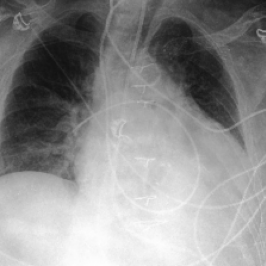

Waterbirds (Sagawa et al., 2020) is an image classification dataset where bird types are associated with a spurious background attribute (water or land). CelebA (Liu et al., 2015) is an image classification dataset, where hair color is an imbalanced attribute with respect to gender. MultiNLI (Williams et al., 2018) is a text benchmark of categorizing two sentences as entailing each other, contradicting each other, or neutral. The spurious correlation is between negation words like “never” and the “contradiction” label. CivilComments (Borkan et al., 2019) is a toxicity text classification dataset containing underrepresented demographic groups. CheXpert (Irvin et al., 2019) is a large-scale medical dataset of chest radiographs with rare pathologies, especially amongst certain minority groups.

We follow standard model choices and dataset splits consistent with prior work (Liu et al., 2021; Kirichenko et al., 2022; Qiu et al., 2023): for Waterbirds, CelebA, and CheXpert, we use ResNet-50 (He et al., 2016) pretrained on ImageNet1k (Russakovsky et al., 2015), for MultiNLI and CivilComments we use BERT (Devlin et al., 2018) pre-trained on Book Corpus and English Wikipedia data.

• J. Irvin, P. Rajpurkar, M. Ko, Y. Yu, S. Ciurea-Ilcus, C. Chute, H. Marklund, B. Haghgoo, R. Ball, K. Shpanskaya, J. Seekins, D. A. Mong, S. S. Halabi, J. K. Sandberg, R. Jones, D. B. Larson, C. P. Langlotz, B. N. Patel, M. P. Lungren, and A. Y. Ng (2019) CheXpert: a large chest radiograph dataset with uncertainty labels and expert comparison. External Links: 1901.07031, Link Cited by: §C.1, §5.1.